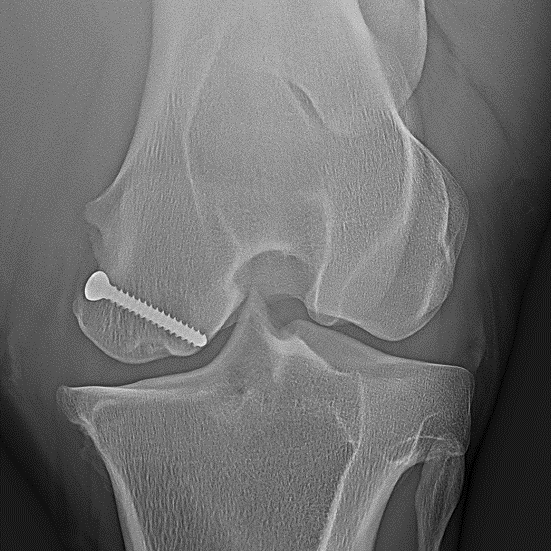

Knochenzysten

- Eine „Knochenzyste“ (subchondrale zystenähnliche Läsion) ist ein rundlicher Substanzverlust im Knochen, meist in Gelenknähe. Sie kann zu Lahmheit und Arthrose des anliegenden Gelenks führen.

- Wenn als Lahmheitsursache eine Knochenzyste nachgewiesen wird, kann sie z.B. durch arthroskopisch gestützte Maßnahmen oder das Einbringen einer Schraube behandelt werden. Die Schraube neutralisiert ungünstige Kräfte im betroffenen Knochen. Dadurch wird die Bildung von Ersatzknochen in der Zyste begünstigt.